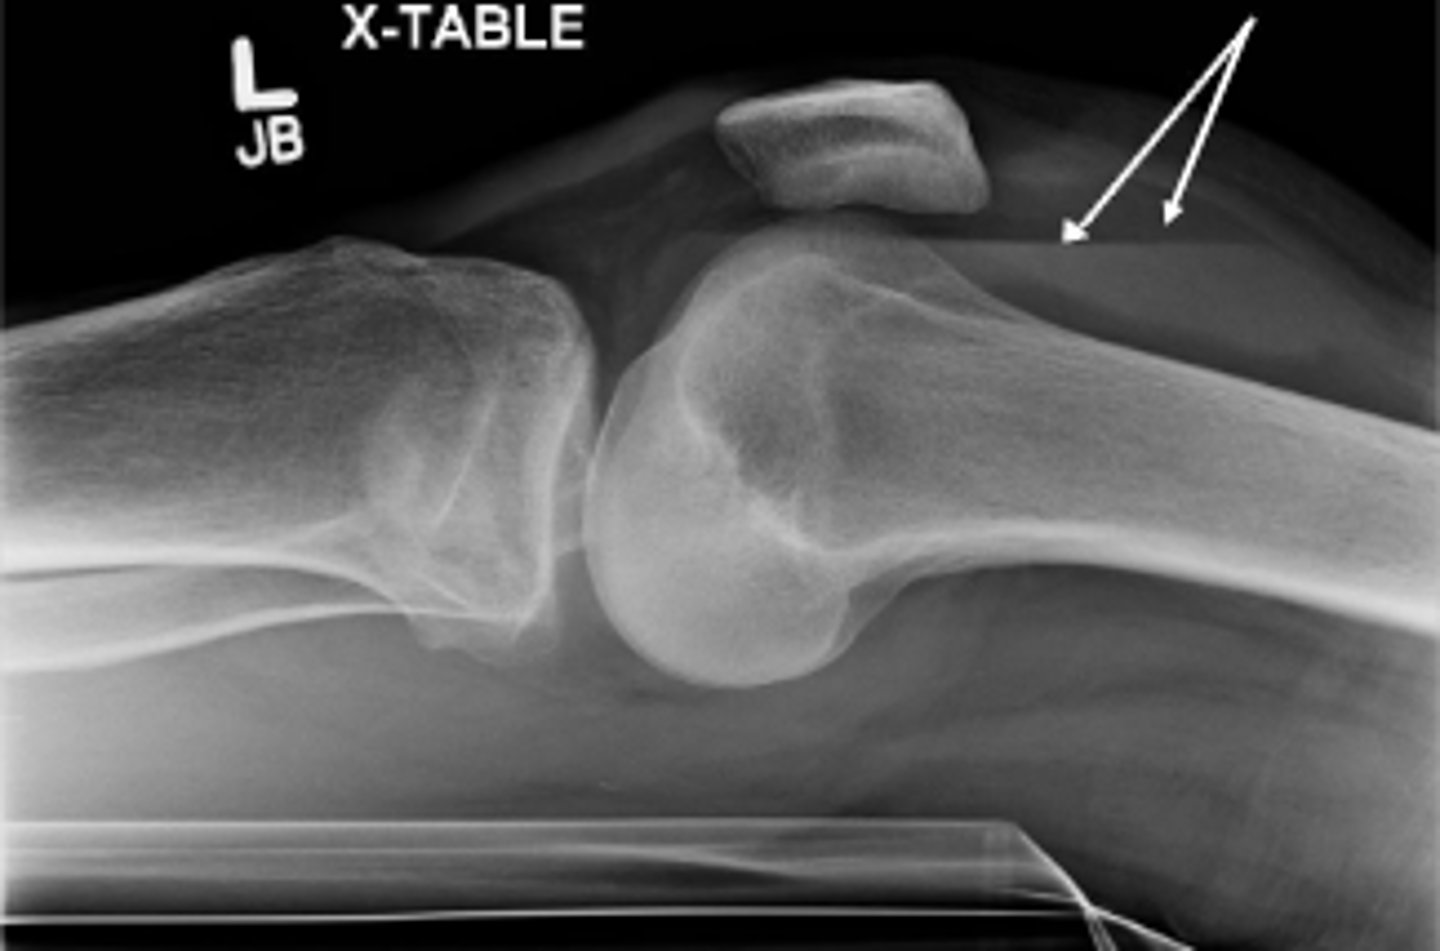

Lipohemarthrosis

What are the arrows pointing to?

Cross table lateral of the left knee

What does 'x-table' mean?